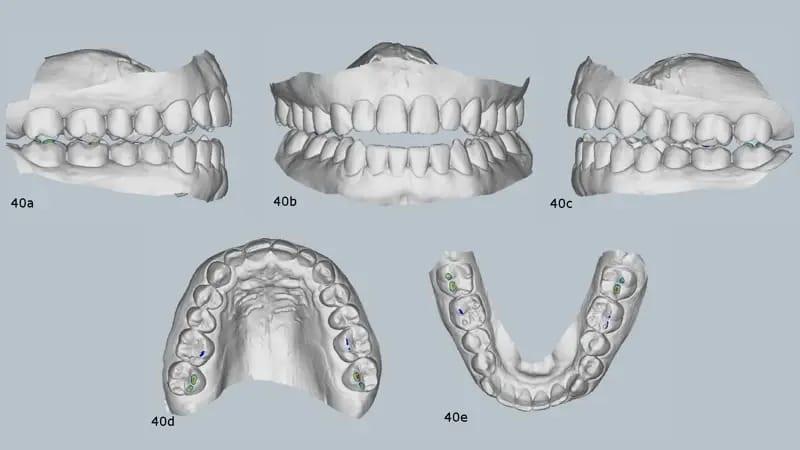

Пациентка пожаловалась на боли в суставах и орофациальных мышцах, головные боли, боли в шее и ночной бруксизм. На КЛКТ были видны небольшие мыщелки с уплощенными суставными поверхностями. Правый мыщелок был расположен немного назад в нижнечелюстной ямке (фото 39). Кроме того, виртуальный артикулятор с использованием системы MODJAW показал, что существует значительное расхождение между максимальным смыканием и центральной окклюзией и что первый окклюзионный контакт произошел на зубе №27 (фото 40).

Фото 40a–e: Предварительное крепление виртуального артикулятора с помощью MODJAW, демонстрирующее несоответствие между максимальной интеркуспацией и центральной окклюзией.